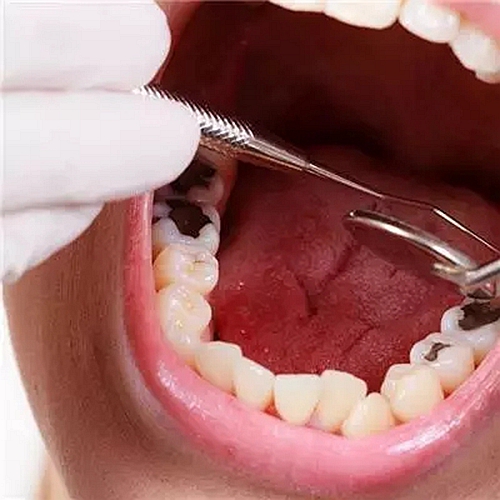

3、易發(fā)齲齒和牙齦炎

不用的那一側(cè)牙齒由于長(zhǎng)期缺乏食物摩擦,而在牙齒間堆積大量的牙垢和牙石,容易發(fā)生齲齒并引發(fā)牙齦炎、牙周炎。